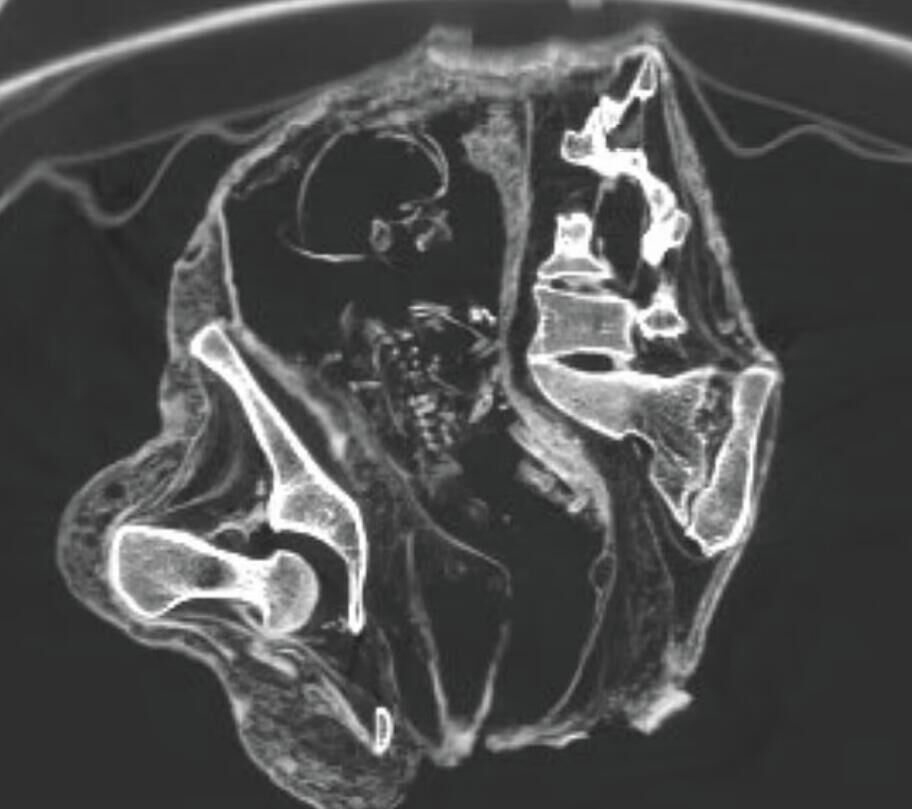

«На снимках компьютерной томографии зафиксирован плод, лежащий на спине головой вниз, в районе живота и грудной клетки, а руки расположены ближе к тазовой области», — говорится в статье.

Женщина, которую ученые прозвали Монтсеррат, умерла 1200 лет назад, спустя месяц после того, как забеременела. Ученые решили сделать КТ из-за необычной позы — она обхватывала живот руками.